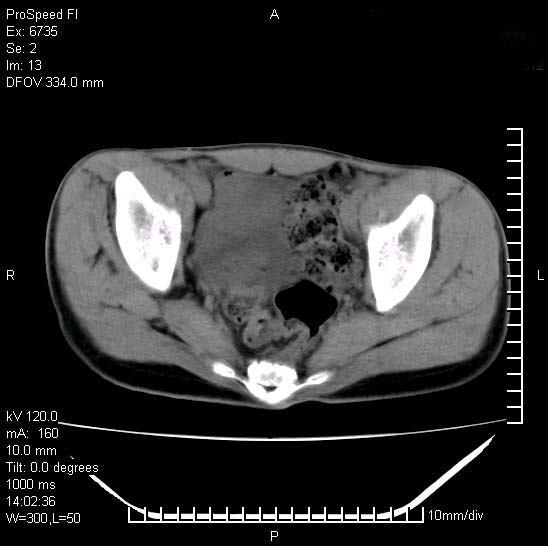

患者自诉胯部疼痛两年余,在当地服用中药,半月前至本院考虑骶髂关节结核,给予抗痨治疗。现发展至右下肢疼痛明显,活动受限,以膝关节处明显,拍膝关节平片无明显异常。

两侧骶骼关节改变,考虑强直性脊炎

左侧骶髂关节面限局性骨破坏,边缘硬化关节腔见钙化物;不出外tb

考虑强直性脊炎,建议查hla-b27

右侧骶髂关节也有类似改变,只是较左侧轻,首先考虑强直性脊柱炎,不除外结核,建议作hla-b27检查。

典型强脊炎改变,髋关节亦有累及

符合强直性脊柱炎表现。